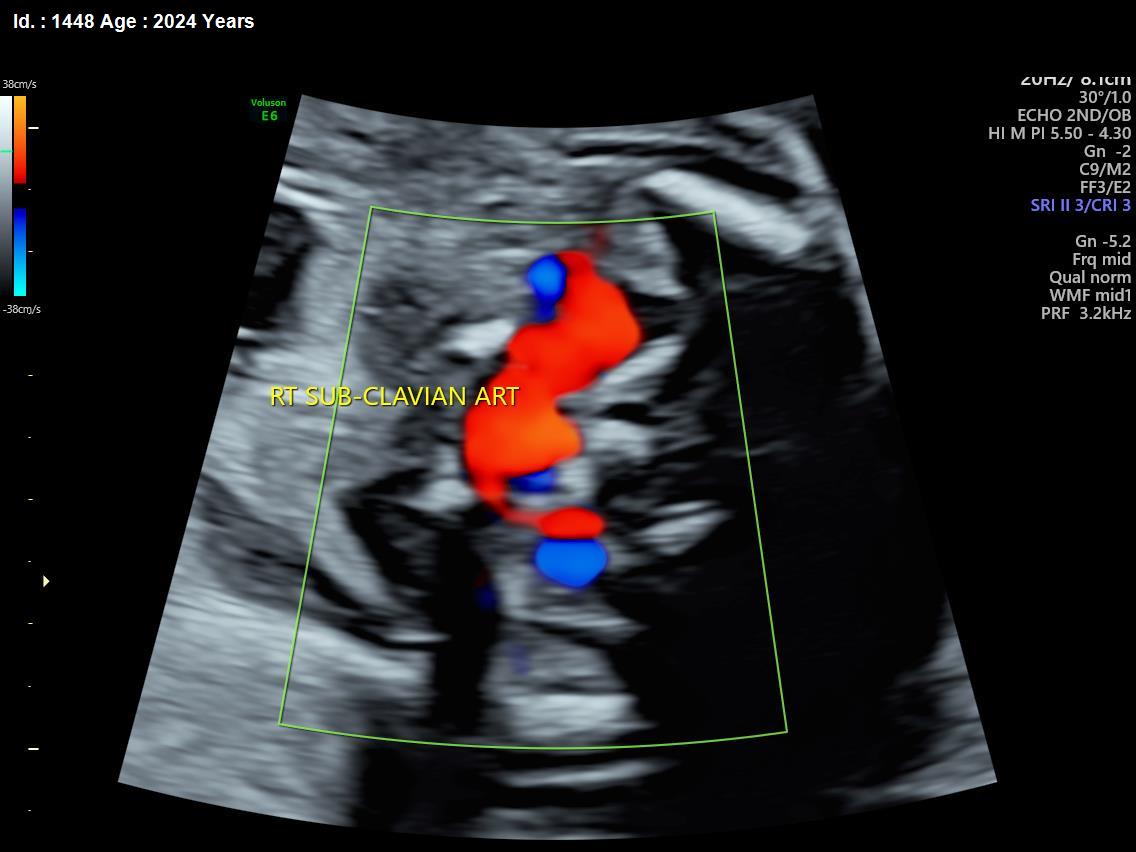

It is a test similar to ultrasound. It allows the doctor to see structure and function of the baby’s heart in detail. It also enables the doctor to see blood flow through fetal heart and cardiac rhythm. The scan is done by a radiologist or a fetal medicine specialist.

A fetal echocardiogram focuses specifically on the fetal heart, providing a detailed examination of its structure and function. In contrast, a standard ultrasound assesses overall fetal development and growth.